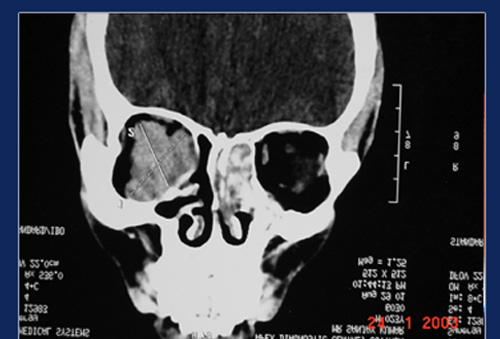

CT scan study of sinuses show typical hyper attentuation inside the sinus cavity called “Metal Dense” shadows. This is due to the fungus trapping heavy metals likes calcium & magnesium. MRI scan show hypointensity of the same areas on T1 – weighted images and signal void on T2 – weighted images.

Expanded sinuses in allergic fungal sinusitis Hyperdense areas suggestive fungal colonies

Fungus shows remarkable ability to expand the sinus walls, so much so the lesions may protrude into the orbit or cranial cavity. Expansion of the ethmoids and frontal sinuses may produce proptosis ( bulging of the eyes). Expansion of sphenoid sinuses may produce loss of vision due to pressure on the optic nerve.